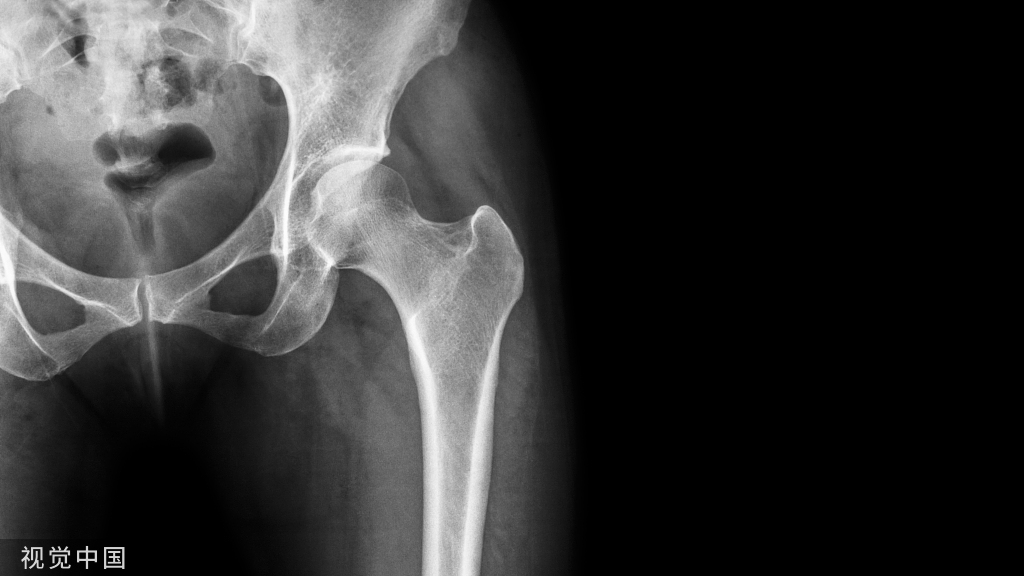

两天的培训课程圆满落幕,学员们感谢老师的倾囊相授,表示参加此次操作坊收获颇丰,意犹未尽,在手术操作方面向前迈进了一大步,未来将以更高的标准、更严的要求完善技能,不断提升专科技术水平,更好地服务患者。